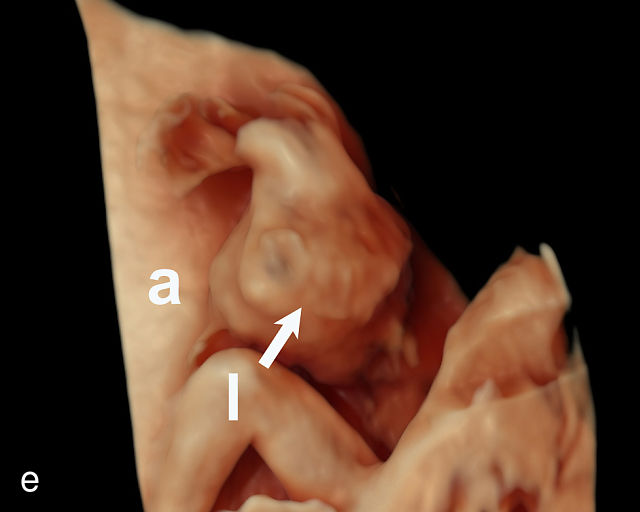

There are three types of vasa previa.30,262 In Type 1, the cord inserts into the membranes rather than the placenta. Unprotected vessels then traverse the membranes over the cervix to insert into the placenta (Figure 21a; Video 12). In Type 2, unprotected vessels running through the membranes over the cervix connect the main placental lobe with an accessory lobe (Figure 21b).263 In Type 3, there is generally a normal placental cord insertion, and unprotected vessels exit one placental edge, run through the membranes over the cervix and then boomerang to insert into the placental edge at another site (Figure 21c).25,28,29,264 Regardless of the type, all these expose the fetus to the same risks.

21